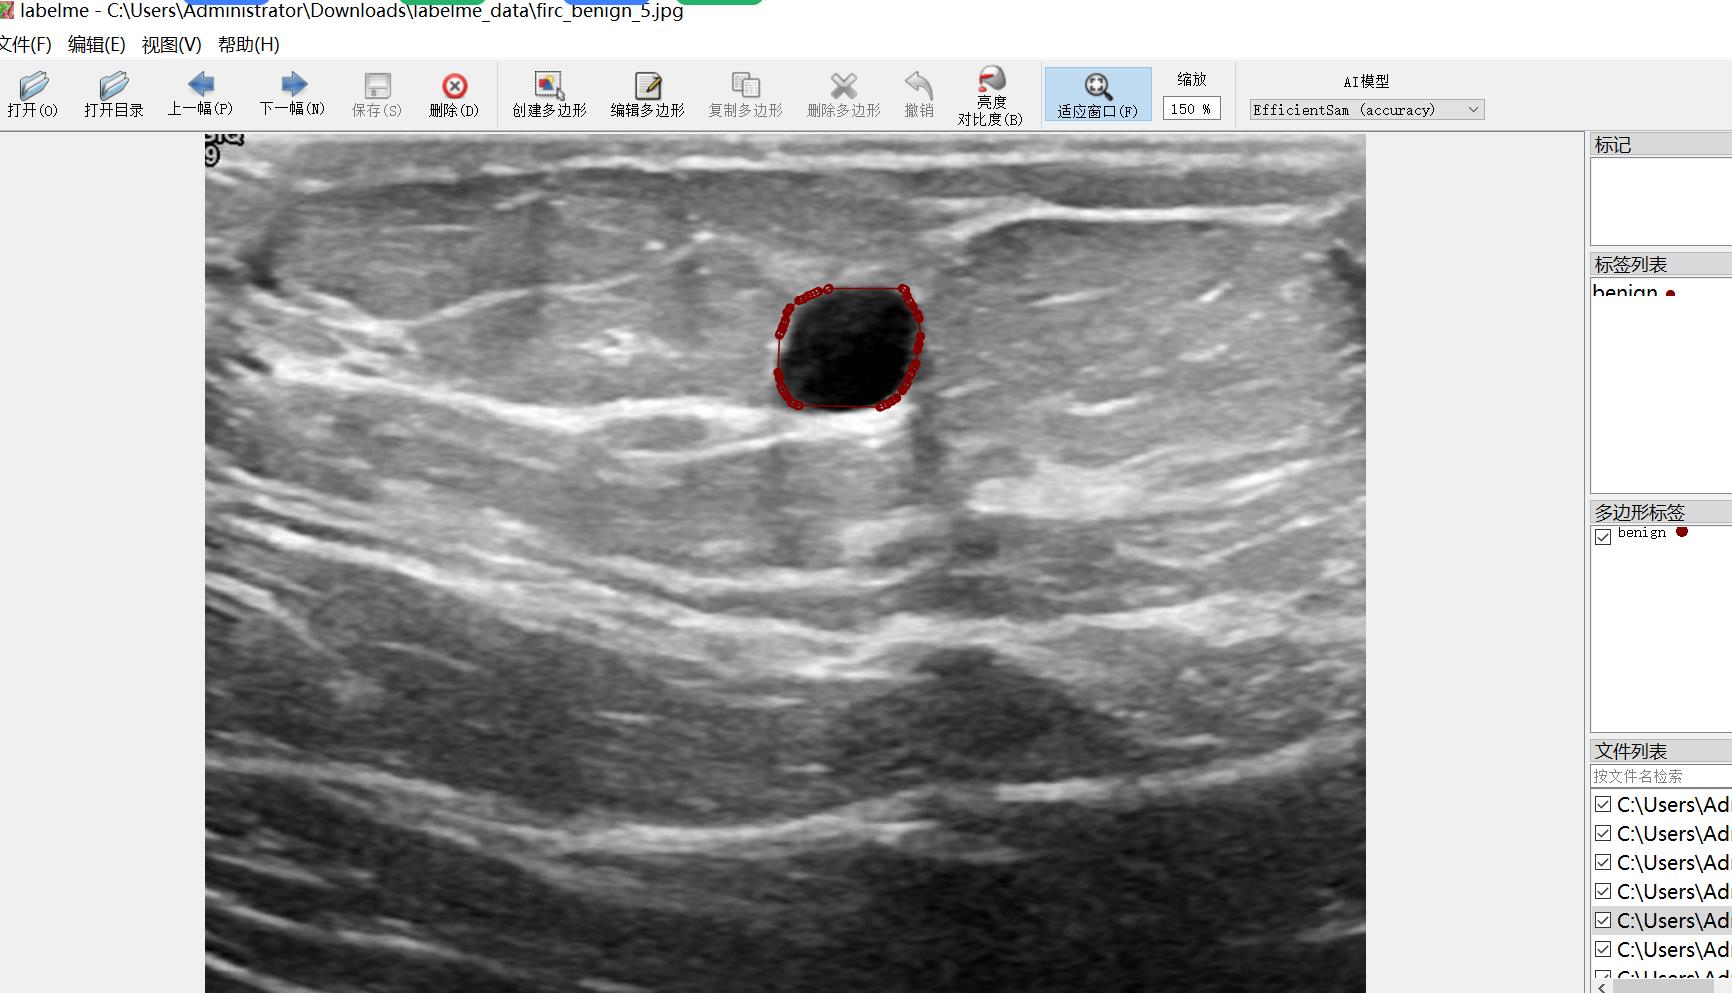

超声波图像乳腺癌识别分割数据集647张2类别

数据集格式:labelme格式(不包含mask文件,仅仅包含jpg图片和对应的json文件)

图片数量(jpg文件个数):647

标注数量(json文件个数):647

标注类别数:2

标注类别名称:["benign","malignant"]

每个类别标注的框数:

benign count = 467

malignant count = 248

使用标注工具:labelme=5.5.0

标注规则:对类别进行画多边形框polygon

重要说明:可以将数据集用labelme打开编辑,json数据集需自己转成mask或者yolo格式或者coco格式作语义分割或者实例分割

图片预览:

标注例子: